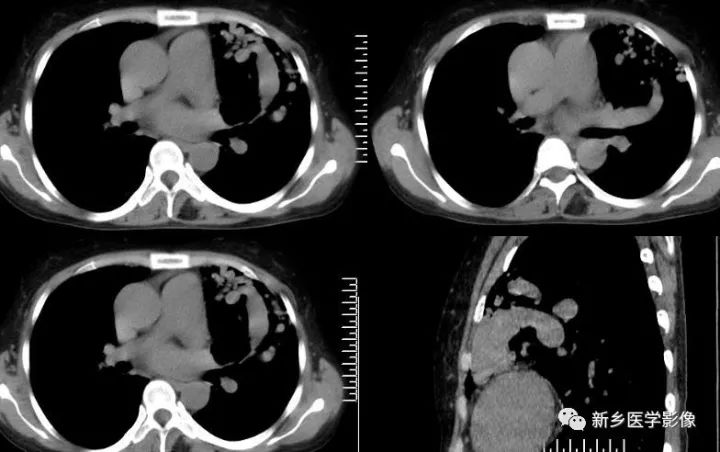

影像学表现

1.结节型 直径<3cm,边缘清晰,密度均匀 2.团块型 直径3-8cm,可有分叶,密度均匀或不均匀 3.弥漫型 肺野散在多个病灶,呈逗点状影,诊断相对较困难 肺动脉造影是诊断金标准,但为有创性。 CT平扫:肺部单发、多发结节或囊袋状影 CTA:①血管蒂征,扩张的血管囊边缘有供血动脉及引流静脉 ②动脉瘤、供血动脉与胸部供血大血管强化一致,引流肺静脉及左心房提前显影。 国外CT表现分型: 1.可分辨解剖结构型 引入动脉及引流静脉 2.结节型 密度均匀结节状影,CT增强病灶直径增大1cm,并与大血管同步强化可确诊。 3.管状型 分隔或不分隔的弓状影 鉴别诊断 1.炎性假瘤:多有炎性病史,边缘呈“方形征”或“刀切征”,增强扫描呈均匀强化,但强化程度不及PAVM。 2.肺癌:边缘分叶、毛糙,周围有浸润,有阻塞改变,增强强化程度不及邻近大血管 3.结核球:边缘光滑或有长毛刺,其内密度较低,可见钙化灶,周围可见卫星灶。增强扫描不强化或边缘强化。 4.肺内富血供结节病灶:主要由支气管动脉供血,时间密度曲线应与左心室与主动脉强化时间一致,且肺内富血供实质结节病灶多为恶性病变,边缘不光整,可见毛刺、分叶 5.肺静脉曲张:为肺静脉局限性扩张,临床很少有症状。一般认为是肺静脉壁先天性缺陷或肺静脉高压造成。病灶靠近左心房,CT扫描两下肺内圆形、椭圆形或管状明显强化,强化程度与左心房一致,无PAVM特征性的供血动脉和引流静脉。